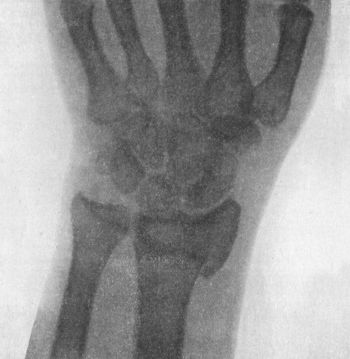

| 48. | Manus Valga following Separation of Lower Radial Epiphysis in Childhood | 109 |

| 49. | Radiogram showing Fracture of Navicular (Scaphoid) Bone | 111 |

| 50. | Dorsal Dislocation of Wrist at Radio-carpal Articulation | 113 |

| 51. | Radiogram showing Forward Dislocation of Navicular Bone | 114 |